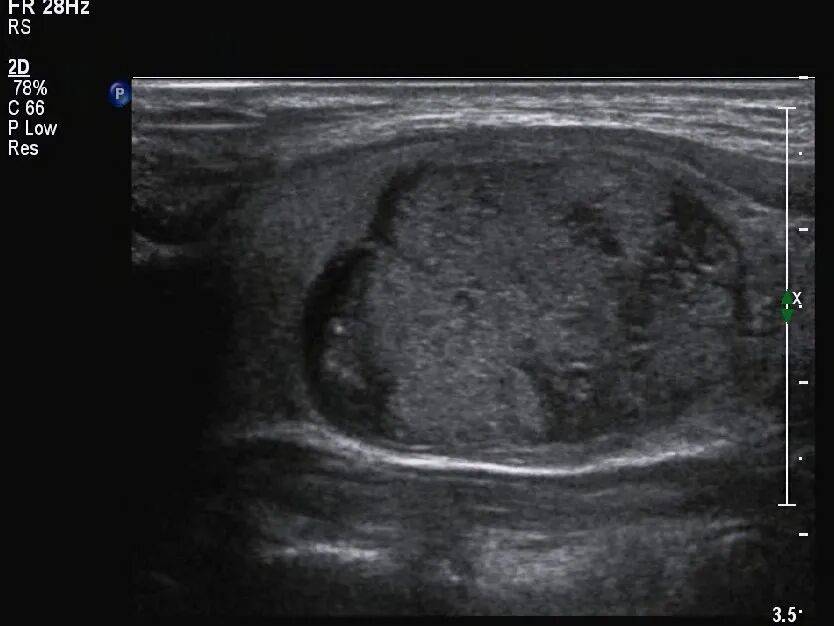

甲状腺形态失常,左侧叶增大,内部回声不均匀,见囊实混合性结节,大小约 33mm×19mm×28mm ,形态规则,边界清,纵横比 <1 ,内部以实性为主,实性部分见少许散在点状强回声(图 1 、图 2 ),结节周边伴低回声声晕,声晕厚度不均匀(图 3 ), CDFI:结节周边见环绕血流信号,内部见不规则分布的血流信号,局部较丰富(图 4 、图 5 )。SMI:结节局部微细血流信号丰富(图 6 )。

图 1 囊实性结节,以实性为主,内见多个散在分布的点状强回声

图 2 结节周边有环绕的低回声带,厚薄不均

接诊医师当时考虑腺瘤并部分囊性变,但结节内的点状强回声,是囊性浓缩胶质形成还是实性部分的微小钙化,难以鉴别,故评估为 C-TIRADS 4a 类结节,建议 FNA 。

如上例中的结节,没有表现出 PTC 最常见的纵横比 >1 的典型特征,反而表现为厚薄不均的低回声晕环,这点在以后的工作中需要加以重视。

本例中的结节为囊实性结节,需要注意区别囊实性结节和海绵状结节,不是只要看到囊实性成分混合的就是海绵状结节,需注意海绵状结节的定义,结节内部不能有实性成分。